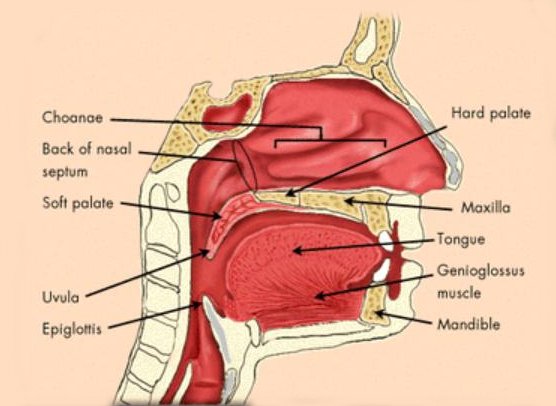

- Surgical removal of tonsils and adenoids will serve to increase the size of the pharynx and to eliminate those possible obstructive structures.

- Surgical removal of any tumors, growths or nasal polyps which may be obstructing the airway.

- Correction of any physical abnormality such as jaw or tissue malformations relieves airflow obstruction in many patients who have sleep apnea.

- Uvulopalatopharyngoplasty (UPPP)

Surgical revision of the uvula, tonsils, soft palate, and soft tissues of the oropharynx may provide significant relief of obstruction in selected patients. - Laser - assisted uvulopalatoplasty (LAUP) Surgical revision of the uvula, tonsils and soft palate, using laser technology may also provide significant relief of obstruction in these patients.